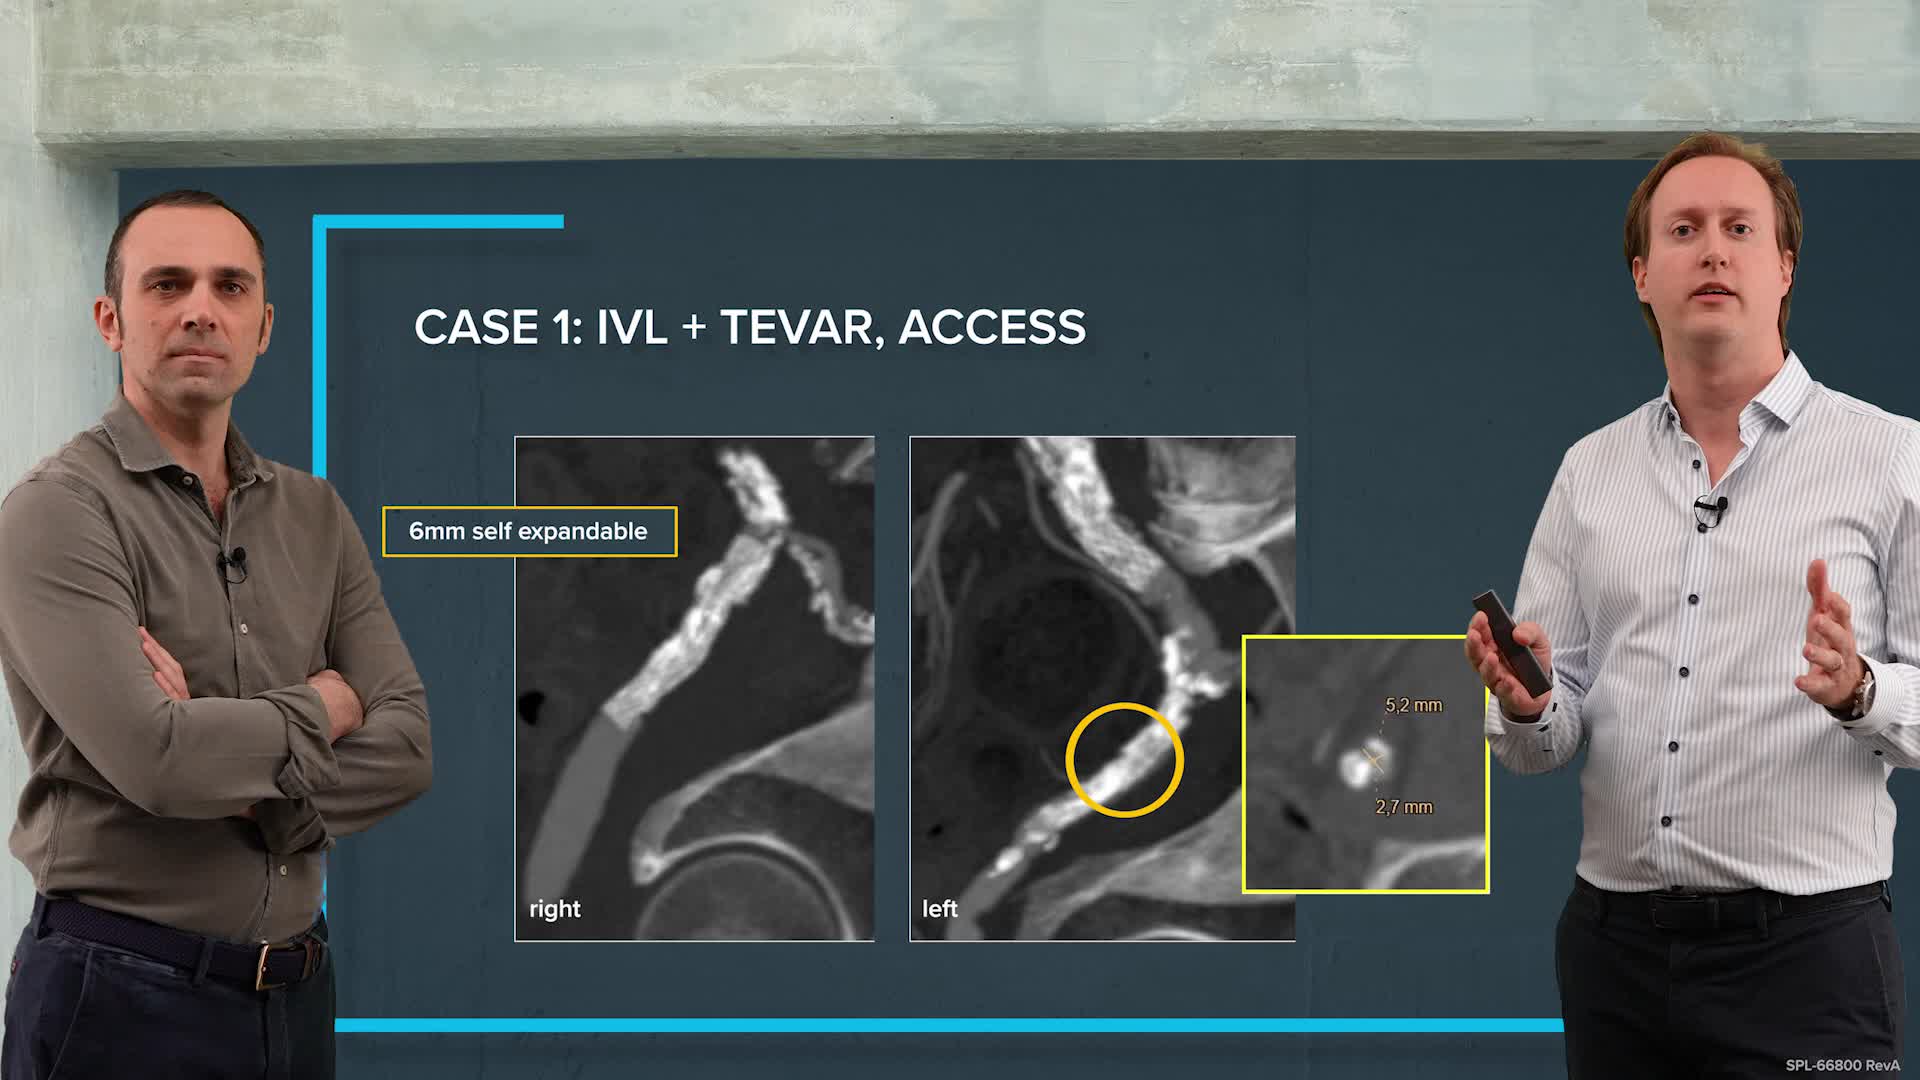

Peripheral IVL learning resources

IVL cracking the calcium conundrum in PAD

Peripheral IVL from the Renals to the Toes